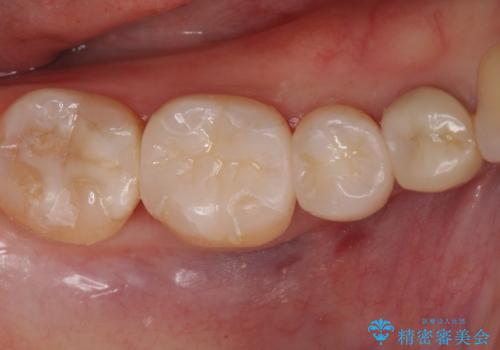

拡大鏡下で詰め物を外し、う蝕がない事を確認して、セラミック(e-maxインレー)で治療を行いました。

- e-maxインレー 7.7万円×2本費用は治療当時の料金となります

セラミックの詰め物(e-maxインレー)は歯質との隙間ができにくく

虫歯の再発リスクが低くなります。

口を開けた時、銀歯が目立たなくなり、大変満足して頂けました。